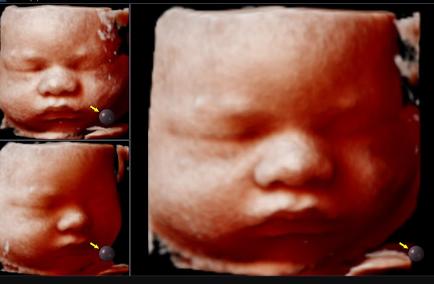

Step into a realm of depth and dimension with our 3d ultrasound Melbourne technology. Amazing Scan's 3D imaging brings your baby's features to life, offering a vivid portrayal of tiny fingers, button noses, and adorable expressions that tug at the heartstrings.

Capturing Moments: 4D Ultrasound

Experience the magic of motion with our real-time 4d ultrasound scans. At Amazing Scan, we go beyond static images, capturing dynamic movements such as playful kicks, gentle stretches, and heartwarming yawns in breathtaking detail.

The Apex of Innovation: 5D Ultrasound